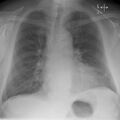

Chest radiograph of a lung with distinct Kerley B lines, as well as an enlarged heart (as shown by an increased cardiothoracic ratio, cephalization of pulmonary veins, and minor pleural effusion as seen for example in the right horizontal fissure. Yet, no obvious lung edema is seen. Overall, this indicates intermediate severity (stage II) heart failure.

Chest X-rays are frequently used to aid in the diagnosis of CHF. In a person who is compensated, this may show cardiomegaly (visible enlargement of the heart), quantified as the cardiothoracic ratio (proportion of the heart size to the chest). In left ventricular failure, evidence may exist of vascular redistribution (upper lobe blood diversion or cephalization), Kerley lines, cuffing of the areas around the bronchi, and interstitial edema. Ultrasound of the lung may also be able to detect Kerley lines.[71]